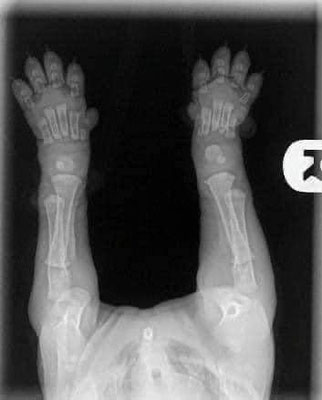

Quando acquistate cuccioli di 8/10 settimane, tenete a mente queste immagini. Le loro ossa non si toccano ancora. Si muovono, così, dolcemente con grandi zampe fluttuanti e movimenti traballanti perché le loro articolazioni sono interamente costituite da muscoli, tendini, legamenti con rivestimento cutaneo. Niente si adatta perfettamente o ha ancora un vero e proprio assetto.

Quando li sottoponete a sforzi eccessivi o non limitate il loro esercizio per impedire loro di esagerare durante questo periodo, non garantite loro la possibilità di crescere correttamente. Ogni grande salto o corsa fuori controllo provoca impatti tra i capi articolari. Un esercizio moderato ed eseguito con razionalità non da problemi.

Quando lasciate che il vostro cucciolo salti su e giù dal divano o dal letto, lo portate a fare lunghe passeggiate / escursioni, state danneggiando le articolazioni. Quando lasciate che il cucciolo scivoli sulle piastrelle senza contenzione adeguata, state danneggiando le articolazioni.

Avete la possibilità di crescerli solo una volta. Un fisico ben costruito è qualcosa che scaturisce da un allevamento di qualità eccellente e da una grande educazione all’esercizio da parte di voi proprietari: in cooperazione.

Una volta che il cucciolo sia cresciuto avrete il resto della vita da trascorrere giocando e impegnandovi in esercizi di maggiore intensità. Quindi mantenete la calma mentre sono ancora cuccioli e fategli un regalo che può essere fatto solo una volta.

Queste sono le lastre di un cucciolo di 2 mesi.

Notate quanto devono crescere ancora le ossa per diventare delle articolazioni finite! Questo è il motivo per cui non dovreste MAI permettere ai cuccioli di saltare, salire e scendere le scale ed esercitarsi troppo.

Svolgere troppe attività che sollecitino le articolazioni in crescita potrebbe causare dei seri problemi ortopedici nel tempo o anche nell’immediato, a giudicare dalla grande quantità di cuccioli che presentano displasie e altri problemi ortopedici.

Ricordate la regola dei cinque minuti: aumentare le attività fisiche di cinque minuti per ogni mese di vita; un cucciolo di 8 settimane non dovrebbe farne più di 10 minuti al giorno, per un cucciolo di 6 mesi ne sarebbero necessari solo 30 minuti; a maggior ragione se il cane è di taglia grossa.

** per attività fisiche si intendono passeggiate, allenamenti, giocare al riporto, correre, ecc.

Godetevi il vostro cucciolo ma ricordate che così come non portereste un bebè di sei mesi a correre una maratona, altrettanto non dovreste fare con il vostro cucciolo.